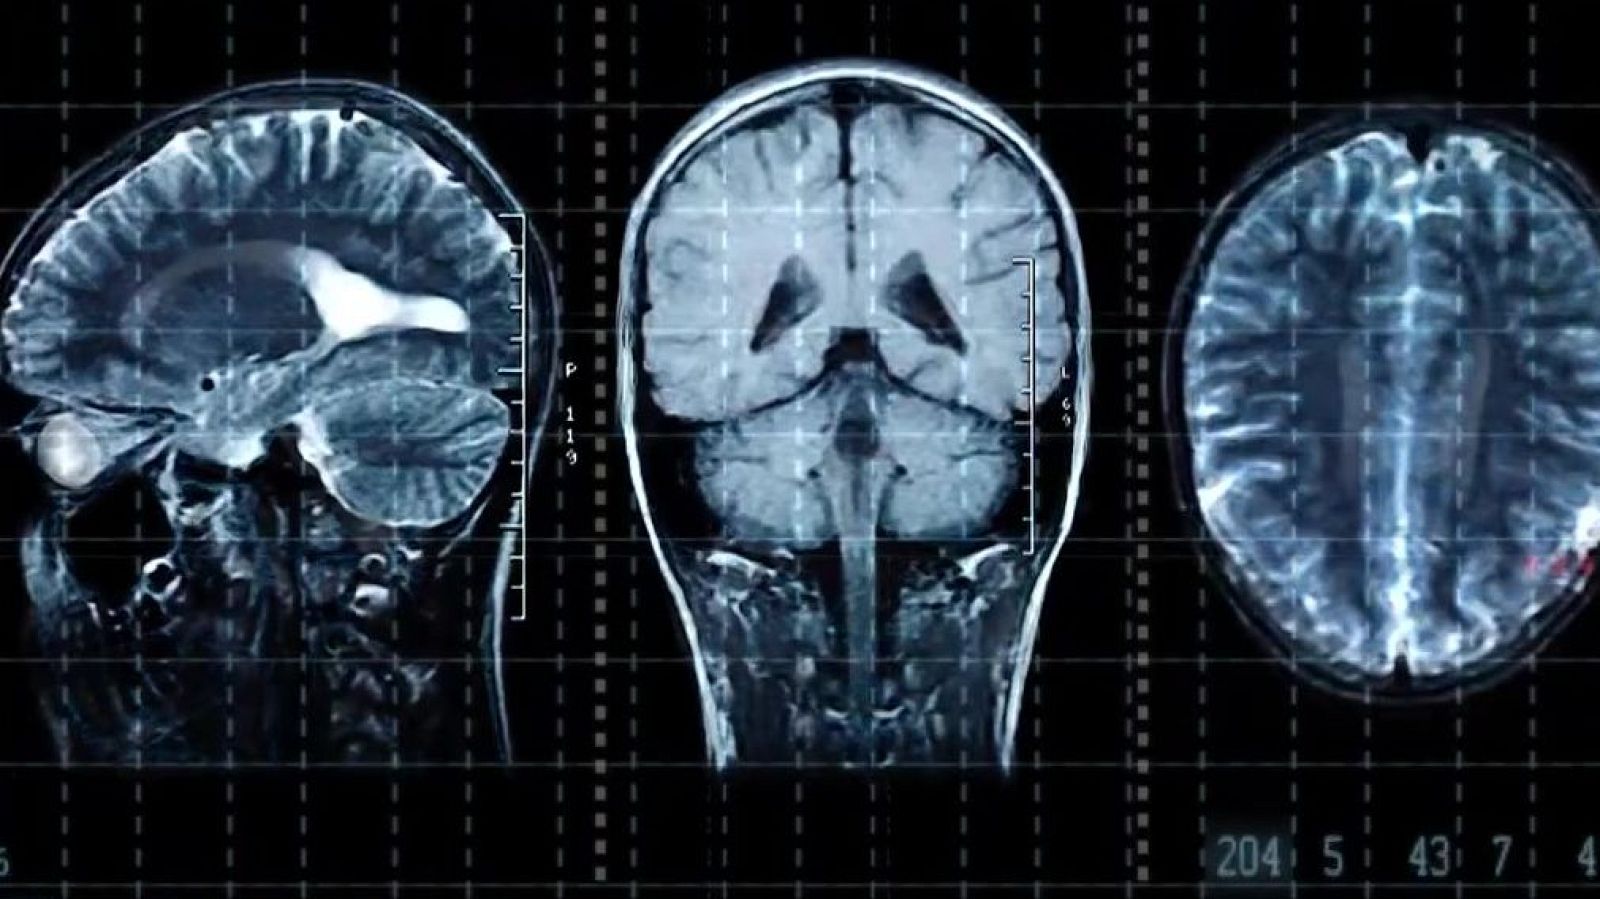

La doctora Alexa Mousley, de la Universitat d'Oxford, ha fet un mapa que mostra les diferències en les etapes vitals del cervell humà, des de la consolidació de la xarxa neuronal fins a l'envelliment. Aquest estudi pot donar peu a la creació de tractaments preventius o terapèutics més eficaços per combatre l'envelliment neuronal. El divulgador científic, Luis Quevedo, explica a 'L'Altaveu' els cinc punts d'inflexió pels quals passa el cervell humà.

Mapa de les cinc etapes del cervell humà de la doctora Mousley, de la Universitat de Cambridge.

Pel que fa al camp de la salut i la medicina, aquest estudi pot comportar un millor tractament de patologies cerebrals. Una de les informacions essencials és que "som més fràgils durant més anys, i això és molt important a l'hora de fer teràpies d'intervenció amb joves i no tan joves", recalca Quevedo. El periodista també remarca que ser conscients de les etapes del cervell permet comparar-nos, mitjançant una ressonància, amb millor informació. "Una cosa és el que posi al DNI, i l'altra és la meva quantitat de joventut o envelliment. Tots coneixem a algú que té 70 anys i està en forma, i gent que amb 40 està feta pols", exemplifica el divulgador científic. En aquest sentit, Quevedo diu que estudis com aquest permeten veure el grau d'envelliment que tenim i, per tant, prendre mesures abans i no esperar a tenir símptomes. "Un cop tens símptomes cognitius, normalment ja vas tard", conclou.